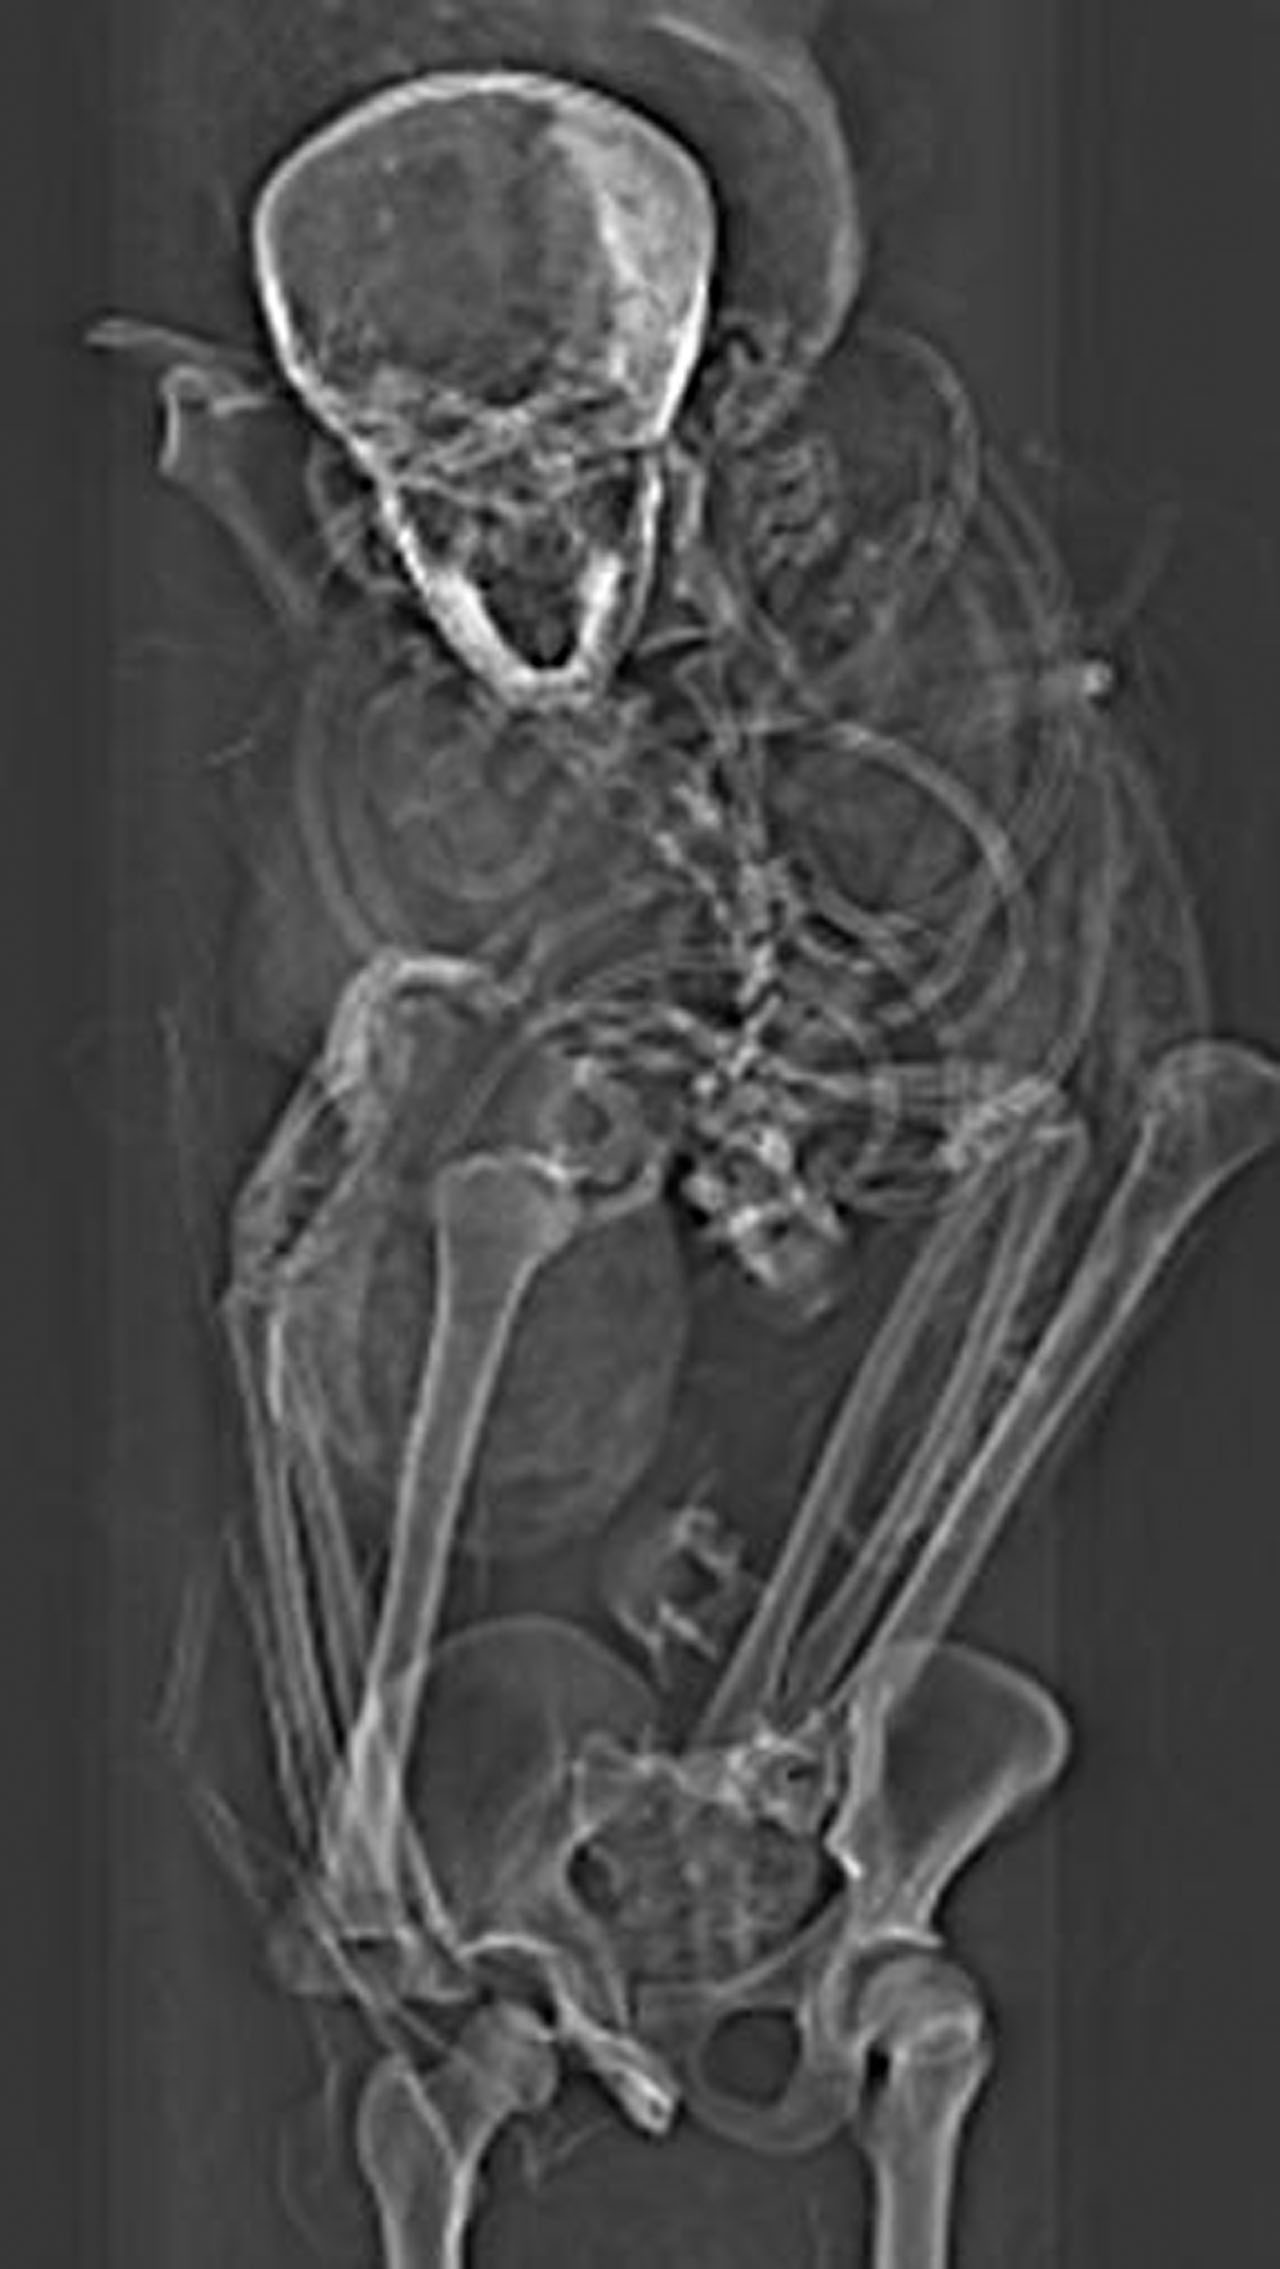

Two general theories exist on how the pharaoh died. One suggests he was captured in battle and executed. Another suggests he was murdered in his sleep. In previous studies, something noted was the mummy's poor condition, implying that the embalming was performed quickly and outside of the royal mummification workshop. Scientists recently used computed tomography, or CT scans of the mummified remains, to reveal new details about the injuries.

The CT scans discovered something interesting in the form of previously undetected lesions that embalmers concealed. The new paper has found that the pharaoh was likely captured on the battlefield, and his hands were tied behind his back to prevent him from defending against the attack. The team believes that the death of Seqenenre-Taa-II was a ceremonial execution.

The ancient pharaoh was about 40 years old when he died, based on morphology revealed in the new CT images. CT images also revealed that the embalmers used a sophisticated method to hide the head wounds under layers of embalming material that functioned like fillers used in plastic surgery. The researchers believe the mummification took place in a real mummification laboratory rather than being performed hastily as previous studies suggested.